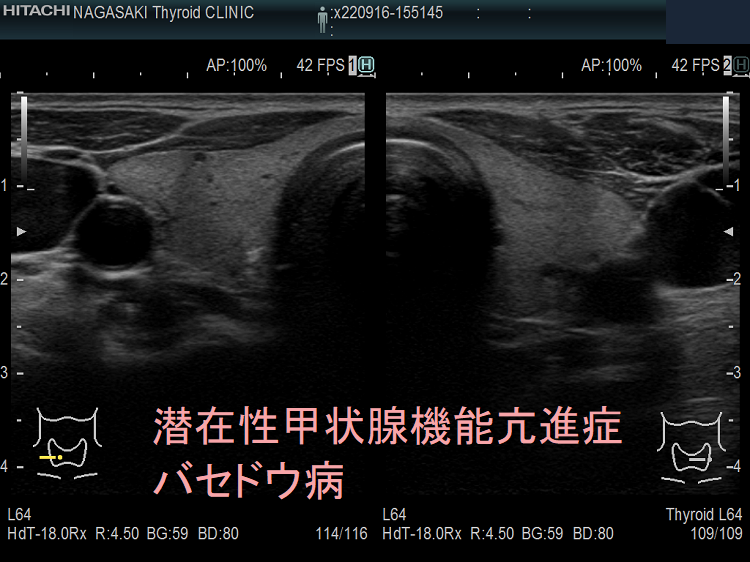

バセドウ病による潜在性甲状腺機能亢進症がある場合は、治療が必要です。医師はおそらく放射性ヨウ素療法またはメチマゾールなどの抗甲状腺薬を処方するでしょう。